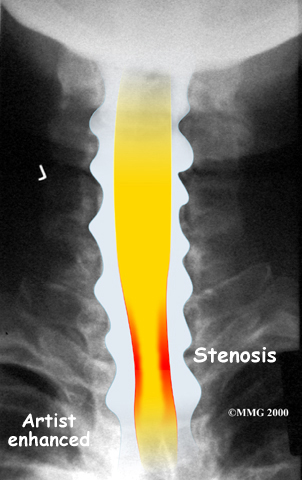

The spinal cord is a column of nerve tissue protected by a bony tube in the spinal column. Conditions that narrow the space in this tube put the spinal cord at risk of getting squeezed. This narrowing is called stenosis. When the narrowing occurs in the spinal column of the neck it is called cervical spinal stenosis, or cervical stenosis. Pressure against the spinal cord as a result of spinal stenosis causes injury to the spinal cord, which is termed myelopathy. Myelopathy is a condition that demands medical attention as it can cause serious problems including problems with the bowels and bladder, changes in the way you walk, and can affect your ability to use your fingers and hands.

The bony spinal canal normally has more than enough room for the spinal cord. Typically, the canal is just less than ¾ of an inch, or 17-18 millimeters around, which is less than the size of a small bottle cap. Spinal stenosis occurs when the canal narrows to around half an inch, or 13 millimeters or less. When the size drops even further, severe symptoms of myelopathy occur. The symptoms of myelopathy result from the actual pressure against the spinal cord itself as well as the reduced blood supply in the spinal cord as a result of the pressure.

X-rays are used to look for the cause of pressure against the spinal cord. X-ray images can show if degeneration has caused the space between the vertebrae to collapse and may show if a bone spur is pressing against the spinal cord.

If more information is needed, a magnetic resonance imaging (MRI) scan may be ordered. The MRI machine uses magnetic waves rather than X-rays to show the soft tissues of the body. This test gives a clear picture of the spinal cord and can show where it is being squeezed. An MRI machine creates pictures that look like slices of the area your healthcare professional is interested in. This test does not require any special dye or a needle.

A computed tomography (CT) scan may also be ordered. The CT scan is a detailed X-ray that lets doctors see slices of bone tissue. The image can show if bone spurs are protruding into the spinal column and taking up space around the spinal cord.